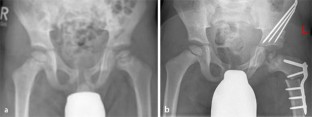

Abb. 2